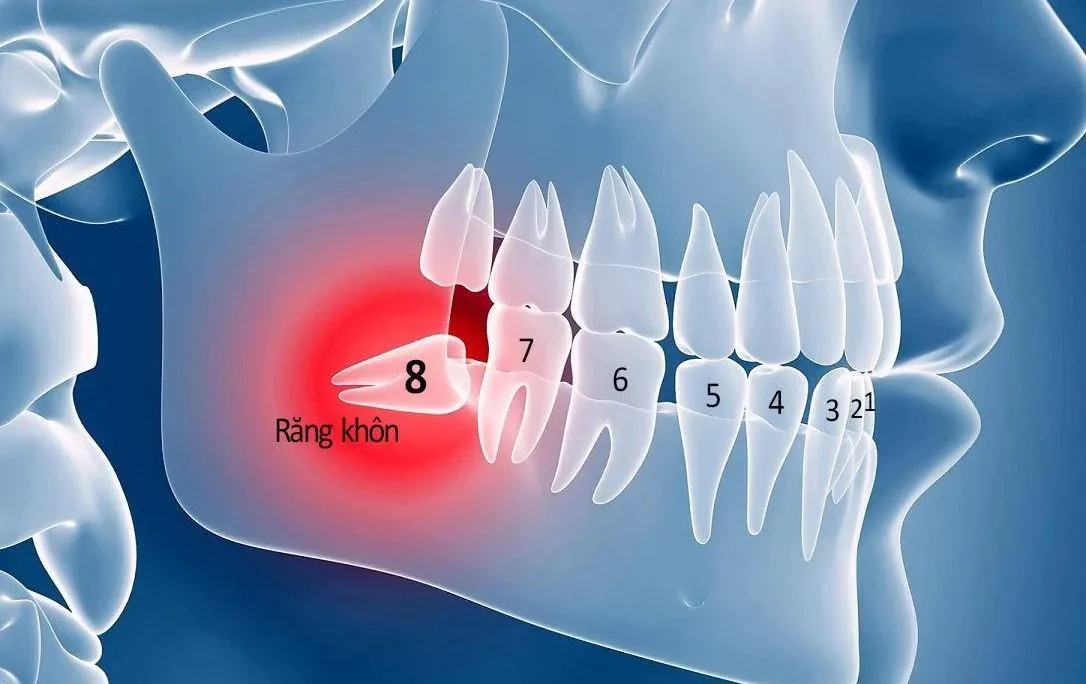

- Cấy ghép xương giúp khắc phục tình trạng xương hàm tiêu biến khi người bệnh mất răng lâu năm, không còn đủ điều kiện để thực hiện đặt trụ Implant.

- Tăng thể tích và tăng độ cứng cho một số tình trạng xương răng yếu, mỏng, không đủ rắn chắc để đặt trụ.

- Một số bệnh lý như viêm nha chu, viêm tủy răng cũng ảnh hưởng tới chất lượng xương hàm, nha sĩ chỉ định cấy ghép xương phù hợp.

- Ngăn ngừa việc xương hàm bị tiêu biến, gây lệch mặt, ảnh hưởng tới thẩm mỹ của người bệnh.